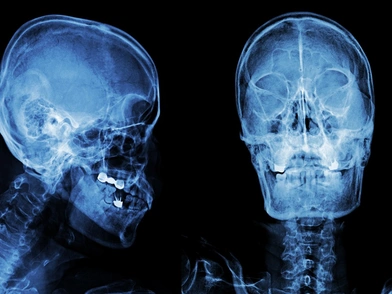

Ακτινογραφία αποκάλυψε ότι του είχε δημιουργηθεί υποδόριο εμφύσημα, μια κατάσταση κατά την οποία ο αέρας παγιδεύεται κάτω από τα βαθύτερα στρώματα των ιστών του δέρματος. Ο άνδρας ευτυχώς δεν χρειάστηκε χειρουργική επέμβαση, αλλά παρέμεινε στο νοσοκομείο για δύο ημέρες ώστε να διασφαλιστεί ότι τα επίπεδα του οξυγόνου του παρέμεναν σταθερά. Πέντε εβδομάδες αργότερα το σχίσιμο είχε επουλωθεί πλήρως.